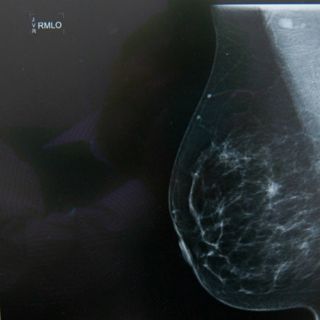

La Elf5 favorece durante la producción de leche y después deja entrar células cancerosas

MADRID, ESPAÑA (30/DIC/2015).- Un equipo de investigadores ha constatado que una proteína que controla la producción de leche durante la

lactancia materna se "descontrola" en el cáncer de mama, lo que favorece la entrada de las